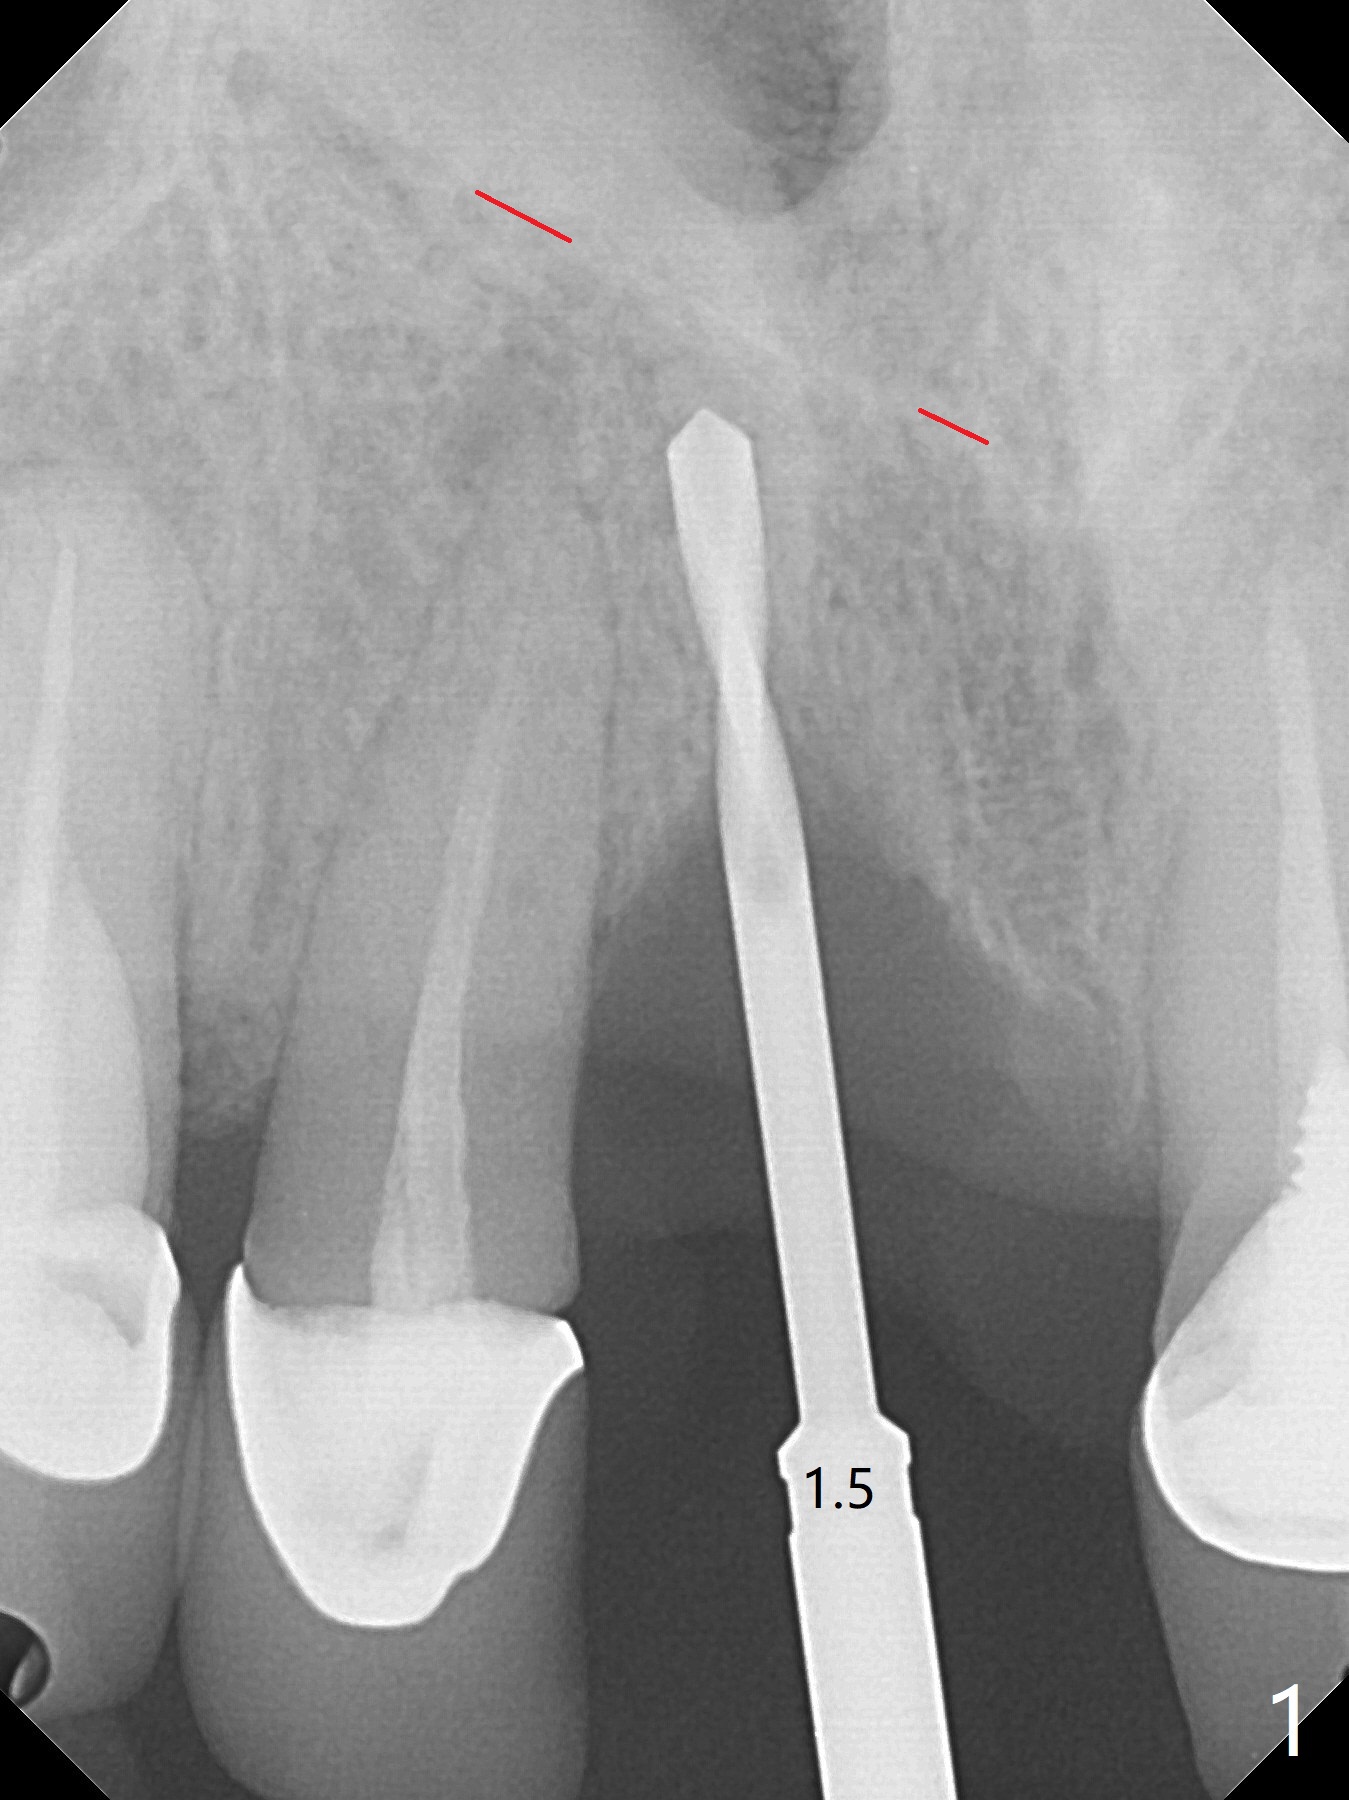

徒手初步钻洞显示方位不对(图一),重新钻洞方位尚可,好像接近鼻底(图二:红线);植入3x11.5毫米一段式植体(图三),3-5个螺纹暴露,植体似乎接近鼻底;旋转植体三趟,植体仿佛卡人鼻底,扭力大约35Ncm,植入粘性骨粉(图四,五:*)前,塞入PRF膜,紧贴颊侧粘膜,促进瘘道愈合。骨粉不仅围绕植体,而且紧贴邻牙牙根(图六(第二轮植骨:overgrafting):<)。病人术后第二周开始使用水牙线,术后三周牙龈健康多了,瘘道消失(图七)。术后六周颊侧骨壁开始塌陷(图八:>),临时牙冠颊侧颈部显得隆起(*)。调整后,牙冠外形改善(图十一至十三),取模前颊侧牙龈缘有可能下降,两个中切牙龈缘可能一致。术后3.5个月骨粉形态(图十四)与术后即刻(图六)有所不同。颊侧牙龈仍红肿轻度触痛(图十五),可能因为临时牙冠不利于局部卫生,所以决定取模制作永久性牙冠。粘固时使用临时胶水,并且涂抗菌素。另外一个可能因素是颊侧骨板薄(图十六:*),细菌感染植体螺纹,永久性牙冠粘固前,拍摄CT(放置cotton roll),必要时,植骨。永久性牙冠远中有缝隙,为了预防病人后悔,使用临时性粘固剂固定(图十七)。Return to No Caries DIO 下一个病例 一段式植体边缘制备 导板与内提升 Xin Wei, DDS, PhD, MS 1st edition 12/22/2020, last revision 06/15/2021